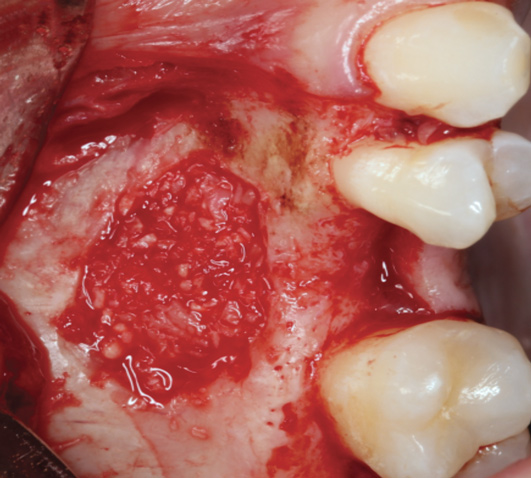

Fig 6. The packing of bone grafting material is made more convenient with improved handling due to the overall change in bone graft consistency when combined with PRF.

FIgure 6

One reported limitation of using PRF alone for sinus augmentation procedures is its use in wide sinuses. Avila et al demonstrated that lateral sinus augmentation procedures performed with an allograft in narrow sinuses (<10 mm) and medium sinuses (10 mm to 15 mm) demonstrated roughly three times more vital bone after a 6-month healing period when compared with wide sinuses (>15 mm) (Figure 4).24 In response to these findings and the clinical experiences of numerous oral surgeons using PRF alone for sinus augmentation procedures, it has been recommended that sinuses >15 mm be regenerated in a combination approach with a bone grafting material. Therefore, all sinuses greater than 15 mm should be regenerated using PRF cut into small fragments with a bone grafting material (Figure 5 and Figure 6).